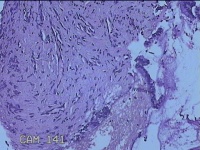

宫颈11点组织

性别

女

年龄

28岁

临床诊断

子宫颈上皮瘤样病变

一般病史

无

标本名称

大体所见

灰白暗红色组织0.7x0.5x0.2cm一块。